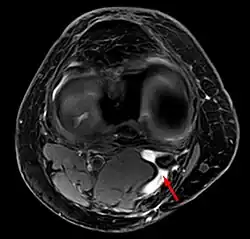

Baker's cyst on axial MRI with communicating channel between the semimembranosus muscle and the medial head of the gastrocnemius muscle. Baker's cyst on axial MRI with communicating channel between the semimembranosus muscle and the medial head of the gastrocnemius muscle.